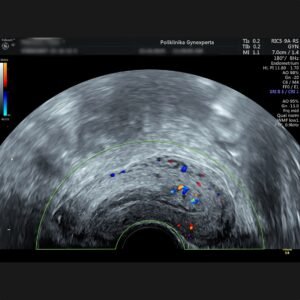

Prikazuje prokrvljenost organa što ma važnu ulogu u razlikovanju benignih od malignih tumora, funkcionalnih cista od cističnih tumora, detekciji izvanmaternične trudnoće itd.

CD DOPPLER

CD GINEKOLOŠKI